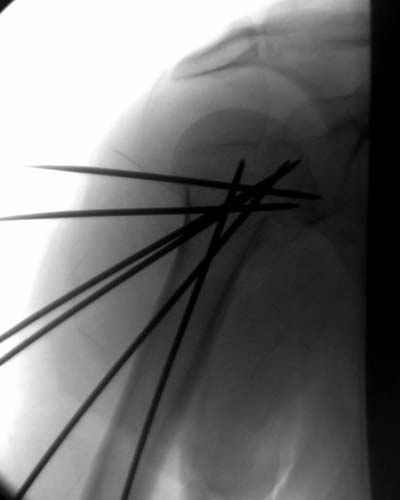

Пока я пользуюсь методикой принятой у нас (методика Сиэтла), также перкутанный спицевой метод, только сцицы 2.8 мм с резбой на конце.

Здесь случай перелома-вывиха плеча, больному 56 лет, после "дважды" закрытой неудачной репозиции, опять же ургентно взяли в операционную, после полного общего обезболивания попытались сделать репозицию, и фиксацию провели спицами.

Больной находился в повязке, примерно напоминяющей косыночную, рекомендованы движения в локтевом суставе и маятниковые движения в плече, спицы удалены в три недели (были случаи миграции)

Больной амбулаторный, предупрежден на случай осложнения АВН головки.